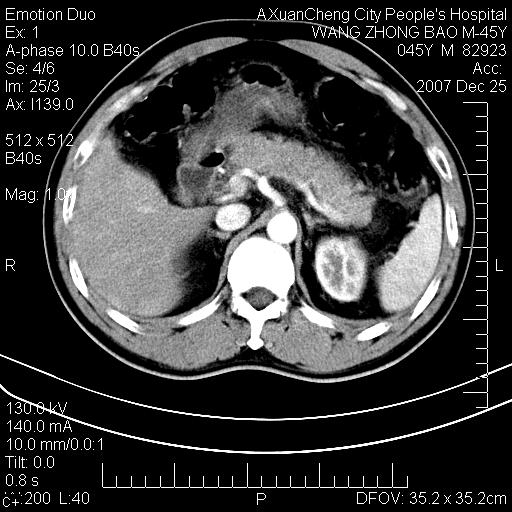

以下是引用qiuleiyu在2007-12-25 18:14:00的发言:[br]胰腺增大,周边渗出改变,肾前筋膜明显增厚,示少量积液.胆囊壁毛糙,周边少许渗出,胆总管壁厚,异常强化,然扩张不明显.结合病程急短;考虑;胆管炎,胆囊炎,胆源性胰腺炎可能大,请结合实验室检查及随访.

以下是引用lisihao在2007-12-25 14:23:00的发言:[br]急性水肿型胰腺炎[br]依据:1、胰腺弥漫性肿大,边缘稍毛糙;[br] 2、双侧肾周筋膜增厚,尤以左侧为甚(重要征象)[br] 3、双侧后胸膜增厚(刺激性炎症);[br] 4、结合病史,查血尿淀粉酶应该可以确诊。